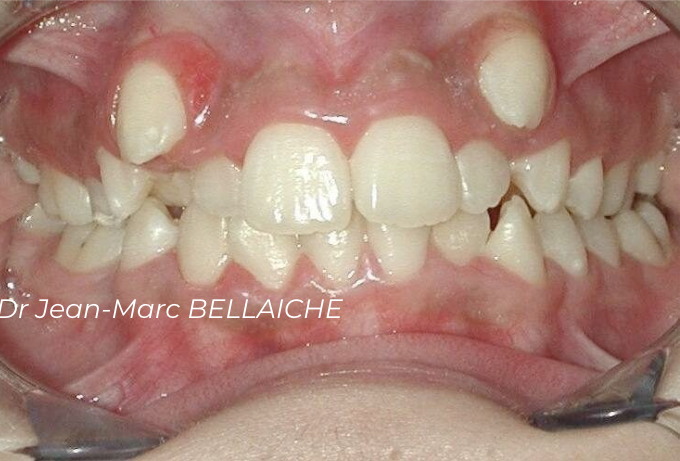

Cas 2 : Encombrement dentaire sévère

Situation "Avant Traitement" : cas d'encombrement associé à un recouvrement excessif des incisives supérieures sur les inférieures empêchant le déroulement normal des fonctions et pouvant être à l'origine de "déchaussements".